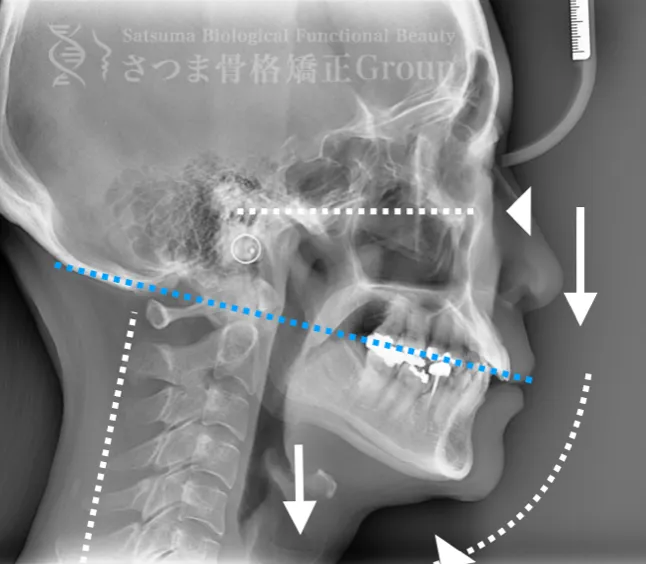

これらの問題を正確に評価するため、当院では セファロシステムによるレントゲン撮影(X-ray images) を行っています。

セファロ撮影によって 顎関節・頭蓋骨・頸椎の位置関係を客観的に可視化でき、施術前の状態を科学的に把握することが可能となります。

施術の前後で撮影したレントゲン写真を比較することで、改善の度合いや変化を一目で確認できます。